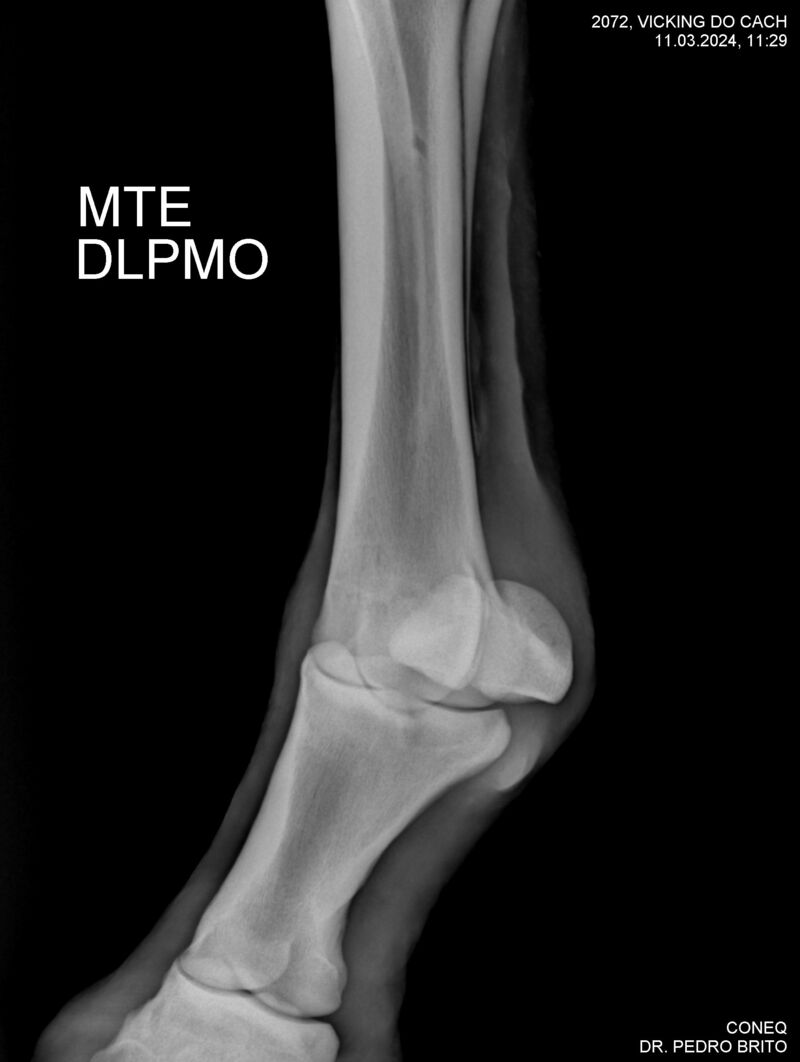

VIKING DO CACH